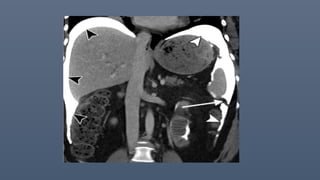

Peritoneal desmoplastic small round cell tumor in a 33-year-old man. Axial contrast-enhanced CT

images of

the abdomen and pelvis show diffuse, irregular, nodular peritoneal thickening (white straight

arrows in A and C), which are most pronounced in the left subphrenic space (black arrowheads in

A), with mild ascites (black straight arrow in A).

Involvement of the peritoneal lining of the falciform ligament (curved black arrows in A and B) and

hepatoduodenal ligament (white arrowheads in B) is noted. Multiple visceral peritoneal and

mesenteric nodules (black arrowheads in C) are noted, with diffuse involvement of the ileal small

bowel mesentery. The tumor is noted to extend into the porta hepatis region (curved white arrow

in B).

Peritoneal desmoplastic smallround cell tumor in a 33-year-old man. Axial contrast-enhanced CT images of the abdomen and pelvis show diffuse, irregular, nodular peritoneal thickening (white straight arrows in A and C), which are most pronounced in the left subphrenic space (black arrowheads in A), with mild ascites (black straight arrow in A). Involvement of the peritoneal lining of the falciform ligament (curved black arrows in A and B) and hepatoduodenal ligament (white arrowheads in B) is noted. Multiple visceral peritoneal and mesenteric nodules (black arrowheads in C) are noted, with diffuse involvement of the ileal small bowel mesentery. The tumor is noted to extend into the porta hepatis region (curved white arrow in B).